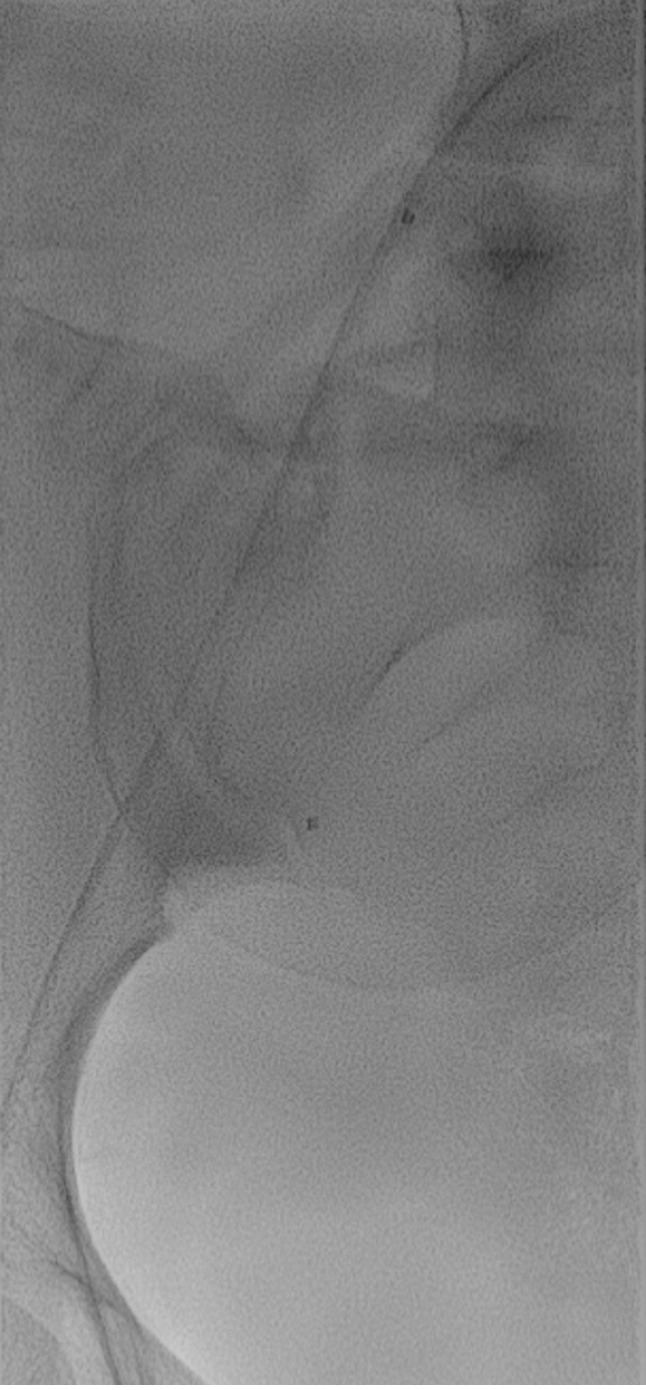

胎盘异常,统称为胎盘增生谱(PAS),由于世界范围内进行的大量剖宫产手术,在全球女性人群中正在增加。PAS是一种罕见但危及生命的疾病,由于子宫壁的绒毛膜绒毛异常浸润至邻近结构,可导致产后出血的风险增加。在PAS患者中,使用球囊闭塞血管内导管对髂动脉进行短暂的预防性阻塞可以帮助控制剖宫产或产后拆除手术中不必要的失血。这篇叙述性小型综述的目的是概述PAS患者血管内球囊预防性闭塞的各个方面,并分析目前关于这一主题的证据。特别地,这个小型综述包括适应症、患者选择、使用的材料和设备类型、技术建议和建议、临床结果和并发症的概述,为每位介入放射科医生、每位妇科医生和助产士提供安全、及时地处理这种特殊情况所需的所有信息。

Placenta abnormalities, which are collectively termed as placenta accreta spectrum (PAS), are increasing globally in the female population due to the large number of cesarean sections performed worldwide. PAS represents a rare but life-threatening occurrence that can lead to an increased risk of postpartum hemorrhage due to the abnormal infiltration of the chorionic villi in the uterine wall up to the adjacent structures. Performing a prophylactic occlusion of the iliac arteries for a brief amount of time using balloon-occlusion endovascular catheters in patients with PAS can help control unwanted blood losses during cesarean delivery or postpartum demolition surgery. The aim of this narrative minireview was to provide an overview of the aspects about prophylactic occlusion with endovascular balloons in patients with PAS and to analyze current evidence on this topic. In particular, this minireview included an overview of indications, patient selection, type of materials and devices used, technical advice and suggestions, clinical outcomes, and complications to give every interventional radiologist as well as every gynecologist and midwife all the information that is needed to address this particular condition in a safe and prompt manner.